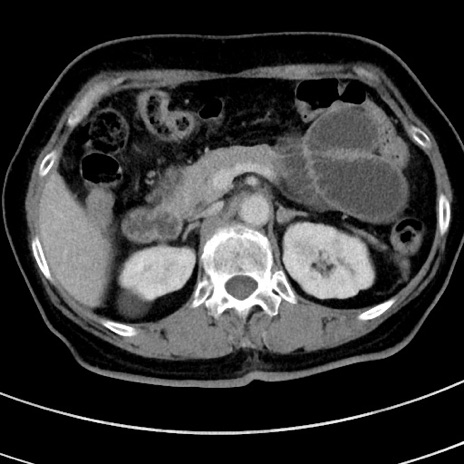

症例9(横断像)

【症例】 60歳代女性

【主訴】むかつき、みぞおちの痛み

【現病歴】3日前よりむかつきがあり、食事がとれない。

【既往歴】糖尿病

【身体所見】発熱なし、心窩部圧痛軽度あるも、腹膜刺激症状なし。

【データ】WBC 7400、CRP 1.92